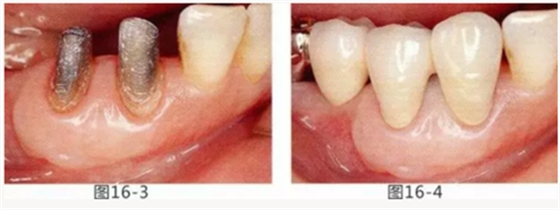

圖16-1 右3,4牙周袋探診值為3~4mm,基本沒有附著齦。右下3部位的系帶也附著在牙頸部附近,由于清潔困難而引發(fā)了炎癥。

圖16-2 由于磨牙部缺失,為了能夠進行固定修復(fù)而在右下6位置植入種植體,制作右下3,4,5,6固定橋冠。為了增加基牙右下3,4周圍的附著齦,在實施FGG同時去除系帶。

圖16-3 獲得了足夠附著齦,可以抵抗刷牙等外部刺激。

圖16-4 獲得充分附著齦,易清潔的狀態(tài)。修復(fù)體之間的鼓形間隙大小均一也使清潔性得到提升。